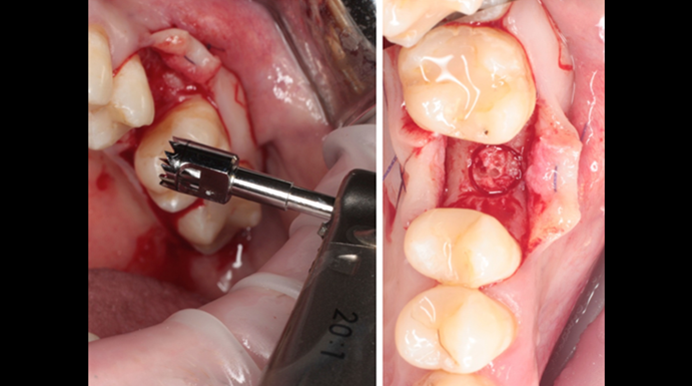

“Thin ridge expansion with minimally invasive surgery!

Use SmarThor & AnyRidge to place a wider diameter implant with minimal drilling after ridge splitting, even in thin ridge under 2mm! “

Clinical case: Ridge splitting technique using SmarThor + AnyRidge as expander

- Courtesy of Dr.Kwang-Bum Park, Korea -

AnyRidge, ridge splitting, GBR, Dr. Kwang-Bum Park, mandibular posterior, SmartThor, Mega-Oss, thin ridge, bone regeneration

AnyRidge implant system. SmarThor, Mega-Oss